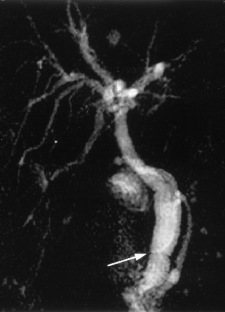

Usual and unusual causes of extrahepatic cholestasis: assessment with magnetic resonance cholangiography and fast MRI

Cholestasis may result from hepatocellular (intrahepatic) disease or biliary tract (extrahepatic) abnormalities. Etiologies causing extrahepatic cholestasis are extremely diverse and invasive procedures, such as endoscopic retrograde cholangiopancreatography (ERCP) and percutaneous transhepatic cholangiography (PTC), were previously required to establish the diagnosis. Due to refinements of magnetic resonance imaging (MRI) techniques, the patient with extrahepatic cholestasis currently can be evaluated noninvasively, and the information revealed frequently exceeds the findings obtained by ERCP and PTC. In this essay, we illustrate the classic MR cholangiographic (MRC) and MRI features of a variety of disorders causing extrahepatic cholestasis, including non-neoplastic disorders of the biliary tract (congenital abnormalities, infectious processes, iatrogenic disorders, and postsurgical complications) and neoplastic conditions (e.g., tumors of the pancreas, biliary tree, liver, ampulla, and regional lymph nodes). In most cases, familiarity with the key MRC features in addition to information obtained via cross-sectional MR images provide sufficient information for adequate lesion characterization.